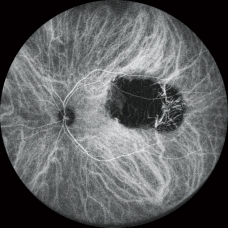

FA和ICG *

高清動態血管造影

可錄制分辨率高達1,024 x 1,024像素,最長時長為120秒的視頻。在同一次測量中也可分段錄制多個短視頻。

FA和ICG同步血管造影

Mirante操作簡便,可同步拍攝FA和ICG影像。實時IR監測方便操作者在熒光產生前調整拍攝位置,降低錯過血管造影早期階段的風險。

自動增益控制(AGC)可同步調整各個FA和ICG圖像的對比度,使動態血流成像成為一個非常簡便的過程。

* 適用于SLO/OCT型。SLO型可選。